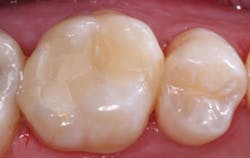

Upon initial examination of the radiograph, only a few minor lesions were observed. When the dentist excavated the caries in the maxillary second molar, the extreme depth of the lesion was able to be seen. This is not an abnormal finding. In spite of the ability to manipulate digital images through magnification, coloring, texturing, and change of contrast, most small lesions and some large lesions are often missed.

Figure 2: On making the initial opening of the mesial surface of the second maxillary molar, the extreme depth of the lesion is evident.